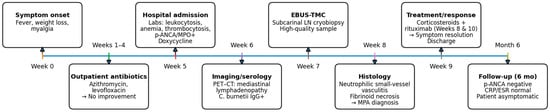

Following histopathological confirmation, immunosuppressive therapy was initiated with high-dose systemic steroid (1 mg/kg/day) and rituximab (1000 mg on days 1 and 15), achieving complete resolution of constitutional symptoms. A chronological summary of the diagnostic workup, interventions, and outcomes is provided in Table 1 (detailed) and Figure 2 (graphical overview).

Figure 2.

Overview of clinical course and key interventions (refer to Table 1 for details).